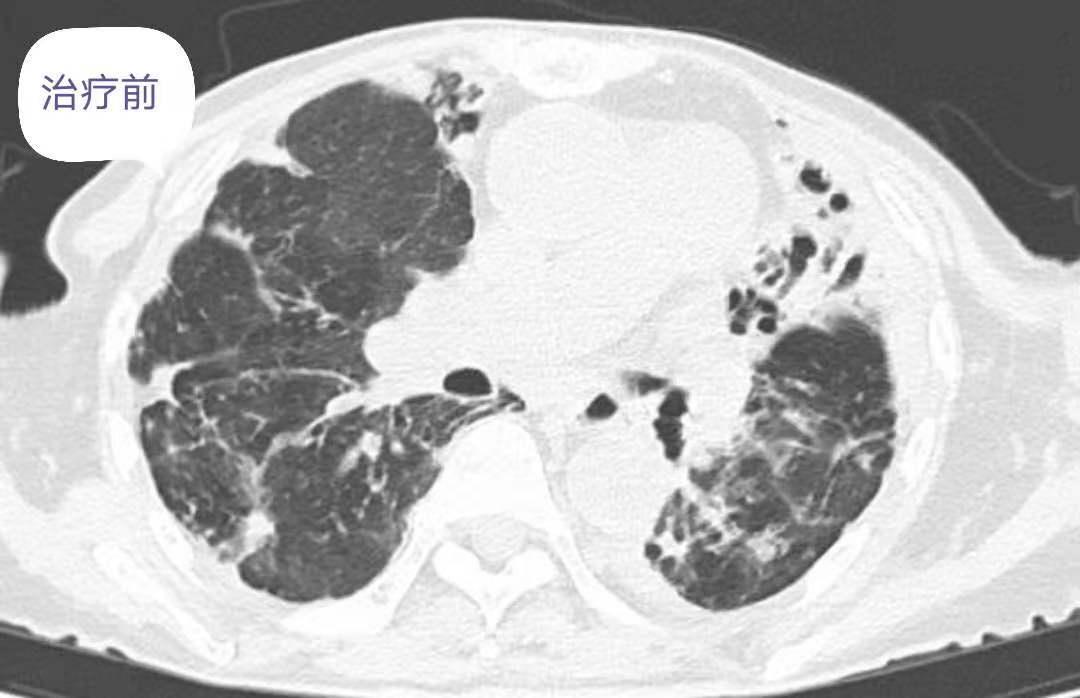

非结核分枝杆菌肺病的综合分析报告

进行性系统性硬化症(PSS)

进行性系统性硬化症(PSS)又称系统性硬化,是一种以皮肤纤维化为主,并累及血管和内脏器官的自身免疫性疾病。病变呈局限性良性皮损,称为硬皮病;有广泛的皮损,并累及内脏器官,称为弥漫性...